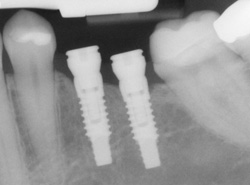

Single or multiple implants

Implants are versatile. If you are only missing one tooth, one implant plus one replacement tooth will do the trick. If you are missing several teeth in a row, a few strategically placed implants can support a permanent bridge (a set of replacement teeth). Similarly, if you have lost all your teeth, a full bridge or full denture can be fixed in your mouth permanently with a strategic number of implants.